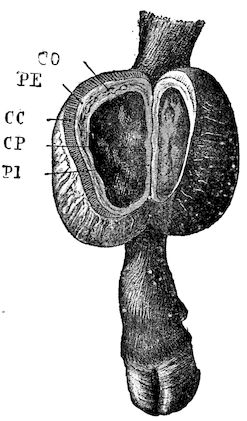

Fig. 8.—Transverse section through the middle region of the face in a pig suffering from osseous cachexia.

18In the final stages, the bones may be cut with a knife, and a time arrives when bony tissue seems completely to have disappeared; thus, as shown in Fig. 8 herewith, it was possible to cut the entire head of a pig into thin slices without the slightest difficulty. All parts of the head had been affected by the softening change.

From the chemical point of view, the diminution in mineral salts and in phosphate of calcium has long been recognised, but the degree of this change varies according to the phase. In human beings the proportions have been estimated as follows: Normal bone, 50 to 80 per cent. of phosphate of calcium; bone in persons suffering from osteomalacia, 5 to 20 per cent. of phosphate of calcium. The changes in the ossein have not been carefully studied. We only know that histologically the ossein becomes fibrillar, and that chemically it no longer retains its normal composition.